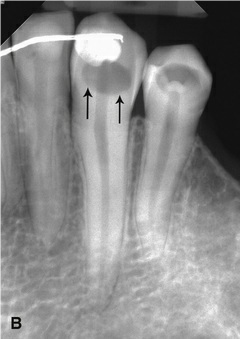

3 / 25

3. (Select ONE OR MORE correct answers)

The radiograph shows evidence of